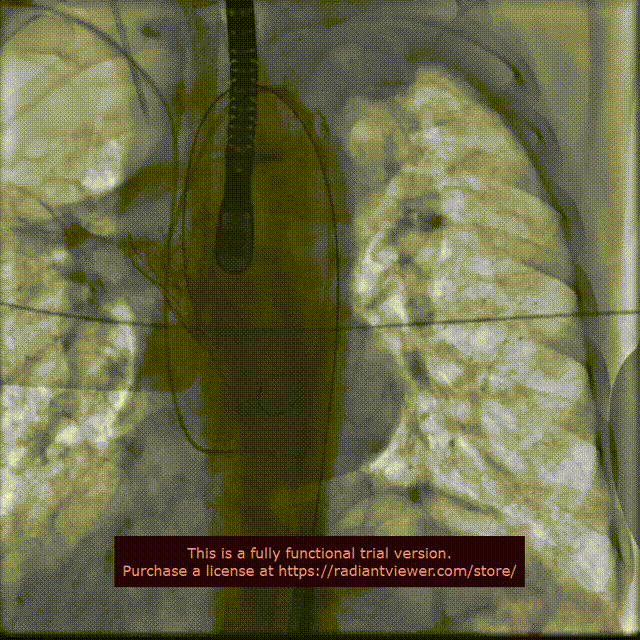

手术过程概览:

行主动脉根部造影后,直头导丝成功跨瓣,选择左冠切线位进行球囊预扩;TaurusElite AV23瓣膜送至主动脉弓,主动脉根部再次造影,并取零位释放位置。

在团队的密切合作下,瓣膜释放到工作位,行主动脉根部造影评估,明确定位良好,瓣膜缓慢释放,瓣架依次稳定脱钩,花冠完全展开。

释放到工作位

瓣膜缓慢释放,稳定脱钩

术后即刻评估:

术后超声评估,血流动力学得到显著改善,手术效果理想。